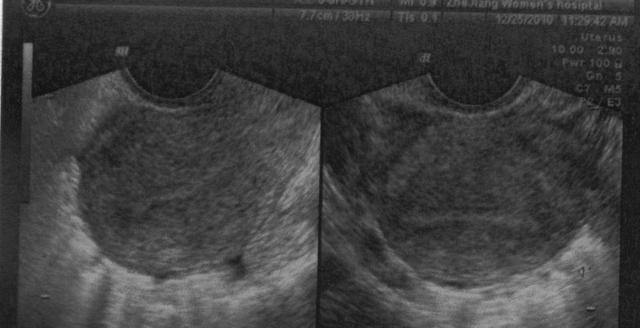

在孕早期的时候,孕妈都会做B超检查,查看存不存在胎停的情况。有些孕妈遇到胎停做了人流,有些孕妈却没有做。

记得在妈妈群里,有这样的一位妈妈说过,她孕早期8周,检查出来没有胎心,医生跟她说是胎停。

第三种反应:胎心消失、HCG下降

如果胎心消失,再加上下降的HCG,就很有可能胚胎已经停止了发育。